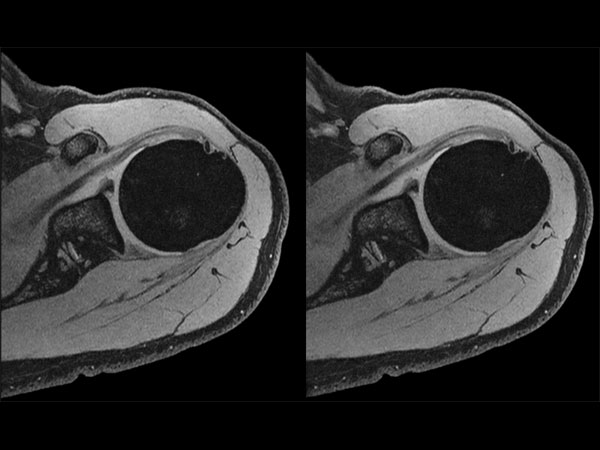

Shoulder imaging with dS Flex coil

Used Solution

• System

• Coil